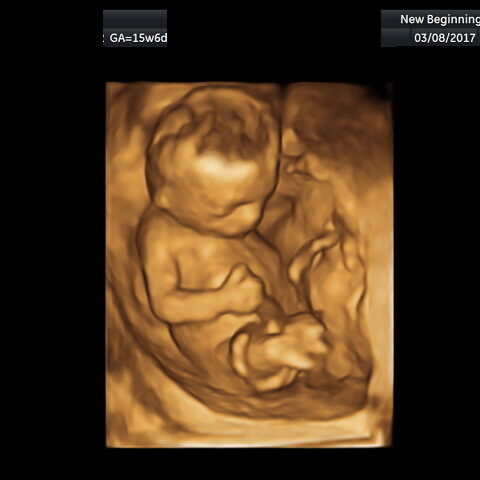

Comparison of 3D and 4D ultrasound images of a fetus.

Our new HD Ultrasound machine has been seen in television commercials and many printed articles from around the world. This machine is the best 2D, 3D, 4D and HD ultrasound machine available. The HD technology will give you unparalleled quality images of your baby that you have to see to believe. Please note, many organizations claim to use “state-of-the-art” equipment, when in fact they use older technology. Ask us about HD technology for your session!